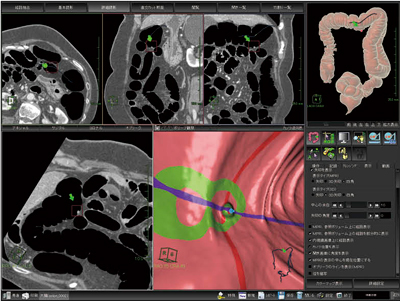

厚生労働省の人口動態統計では,わが国の大腸がん死亡率は,女性では2004年から胃がんを抜いてがん死因の1位になり,男性では肺がん,胃がんについで3位となった。術前検査として用いられることが一般的であった大腸3D-CT検査は,大腸がんスクリーニングへの拡大が期待され,これを補助するのに非常に有用なソフトウェアが“大腸解析ソフトウェア”である(図2)。

大腸解析ソフトウェアでは,大腸の自動抽出,フライスルーの自動検索を読み込みと同時に行ってくれるので,ユーザーは読影だけを行えばよい。残渣に埋もれたポリープを観察したいときは,電子クレンジング機能を用い,オリジナルの画像と電子クレンジングした画像を比較して確認することも可能である。また,2体位画像の同時比較が,随時に,かつ,素早く行え(図3),その画面でポリープなど観察したい箇所を指定するだけで,MPR像を簡単に作成でき,その病変の浸潤度を観察することが可能である。

結果の出力機能も充実しており,画像のDICOM保存,動画作成,レポート作成も一連の流れで行うことができる。

当社のネットワーク型ワークステーションを用いれば,大腸の自動抽出からフライスルー自動検索までと,読影を別々の場所で分担して行うことができ,ユーザーの負担を分散することが可能である。

図2 大腸解析ソフトウェア